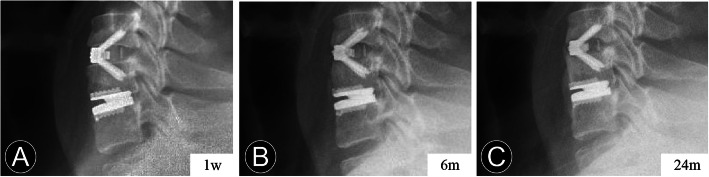

Fig. 1.

A 51-year-old woman who underwent contiguous 2-level hybrid surgery at C4-C6. b and c Preoperative dynamic radiographs show that a loss of intervertebral disc height and decrease of segmental mobility occurred at C5–6. Thus, fusion was performed at C5–6 and cervical disc arthroplasty was performed at C4–5. e and f The immediate and 6-month postoperative lateral radiographs show the peri-prosthesis bone loss was found at the replacement level. e, f, g, and h The measurement method for the degree between the prosthesis position and posterior vertebral line. The postoperative lateral radiographs obtained at 1 week, 6 months, 12 months, and 55 months after surgery show the progression of implant subsidence